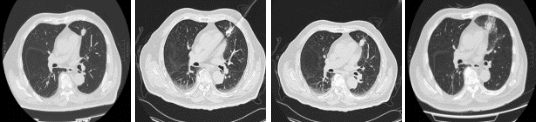

77岁的陈老伯是一位刚走下手术台不久的“抗癌老兵”。1年半前,他经历了前列腺癌根治术,本以为可以安享晚年。然而,在最近的一次术后随访PET-CT检查中,医生发现他左肺上叶那颗原本“沉睡”的结节突然代谢增高,这意味着恶性肿瘤再次找上了门。尽管陈老伯的肺部病灶尚属早期,但其位置紧邻心脏,随呼吸与心跳同步移动,传统消融因易损伤心脏及大血管,风险极高。面对这一困局,陈老伯在家属陪同下辗转求医,最终求助于周彩存教授团队。

周彩存教授团队在充分评估后认为,病灶虽不大,但位于心脏旁“生命禁区”,临近重要心脏结构和大血管、大气道,任何物理局部处理手段都有一定风险。为此,团队决定启用穿刺手术导航定位系统(简称RC120),凭借其“CT影像与智能传感一体化”技术,解决传统定位方式的痛点,为陈老伯的肺部诊疗提供了更精准、更安全、更便捷的选择。